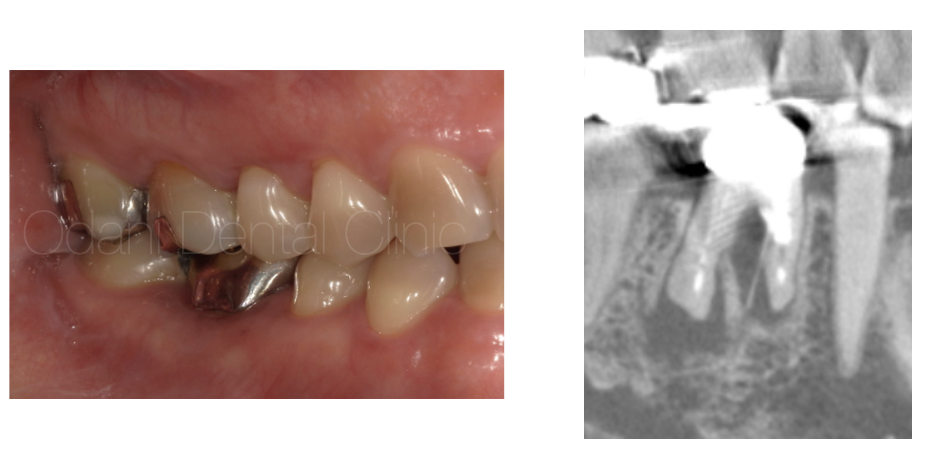

こちらの患者様は、神経のない歯にヒビが入ってしまい、長期間放置したことで感染により骨が吸収してしまっています。歯を残すことが難しく、残念ながら抜歯することになりました。

感染を起こした歯を無理に長期間置いておくと、抜歯後に骨と歯茎に大きな凹(へこ)みを生じます。抜歯後2ヶ月で歯ぐきの治りを待ってから、インプラント手術を行いました。

写真のように、骨がない場合はインプラント埋入時に治療オプションとしての骨移植材を用いて、骨造成(骨を作る処置)を併用しなければ、インプラントの一部が骨から露出して治療後に汚れの溜まり場が残り、長期安定は得られません。